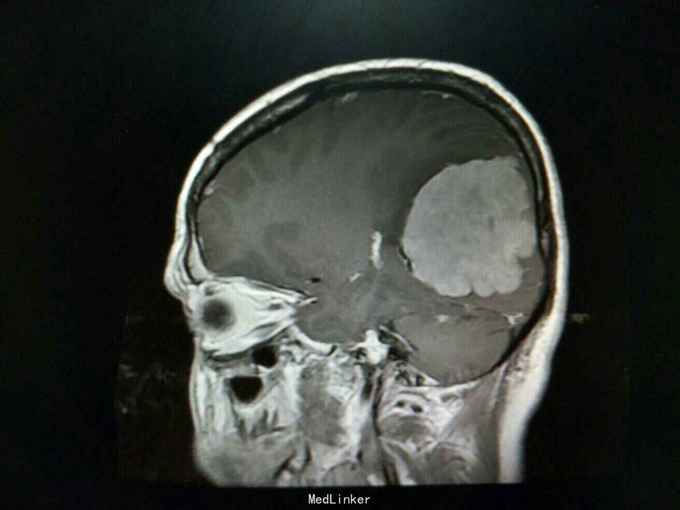

患者50岁男性,因“反复头晕、头痛伴记忆力下降4月余”入院。

查体:生命体征平稳,神经系统检查未见明显异常。辅助检查:头颅增强+血管MR扫描提示:双侧额顶叶、侧脑室周围见斑片状异常信号区,T1WI呈等信号,T2WI及T2-FLAIR呈稍高信号。左侧枕部大脑镰旁可见团状软组织肿块影,边界清,形态不规则,呈分叶状,大小约62mm×49mm。病灶T1WI呈等信号,T2WI呈稍低信号,周围可见脑脊液环绕;增强扫描病灶明显均匀强化。病灶占位效应较明显,左侧顶枕叶脑实质受压向内移位,左侧侧脑室受压变形。中线结构稍向右移位。余脑实质未见异常信号灶。颅骨未见明确异常。头颅MRA:病灶内可见多发迂曲血管影,可见大脑后动脉及脑膜动脉供血。双侧大脑前、中、后动脉管壁光滑,走行自然,管腔未见明显扩张或狭窄,未见动脉瘤征象。Willis环未见异常。1. 左侧枕部大脑镰旁占位性病变,考虑脑膜瘤可能性大;2. 轻度脑白质疏松;2. 头颅MRA提示病灶血供来自左侧大脑后动脉及脑膜动脉;余未见异常。

诊断:左枕部大脑镰旁脑膜瘤 处理:左枕部开颅大脑镰旁脑膜瘤切除术

术后病理提示:(左顶枕叶肿瘤)脑膜瘤,上皮型,WHOⅠ级。大脑镰旁脑膜瘤是指位于大脑纵裂并与大脑镰相连的一类临床上常见的脑膜瘤,常突入一侧大脑半球内,有时可向双侧发展。也有少数肿瘤呈扁平型,在大脑镰内浸润性生长。肿瘤可由大脑镰脑膜动脉供血,也可由脑内动脉供血,其前部可来自眼动脉分支,后部来自枕动脉,中部可有脑膜中动脉供血。在肿瘤基底和附近的大脑镰内有多条扩张的静脉。